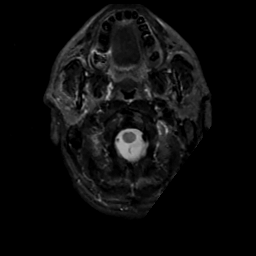

MR Study #6, March 17, 1991 -- Slice #1

[Home][Help][Clinical][Tour 1][Tour 2] Slice 1